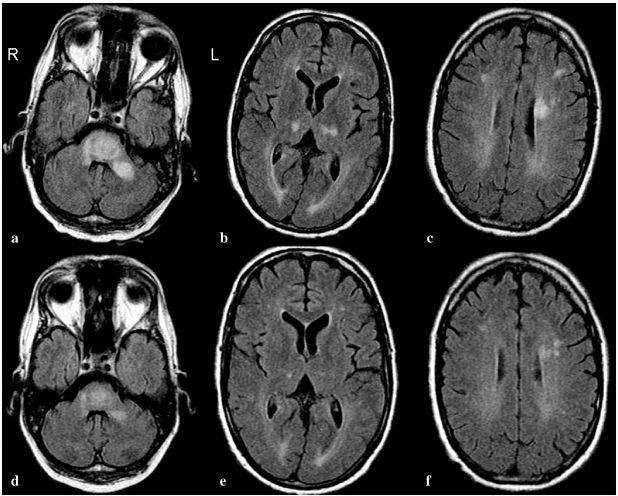

adem--案例